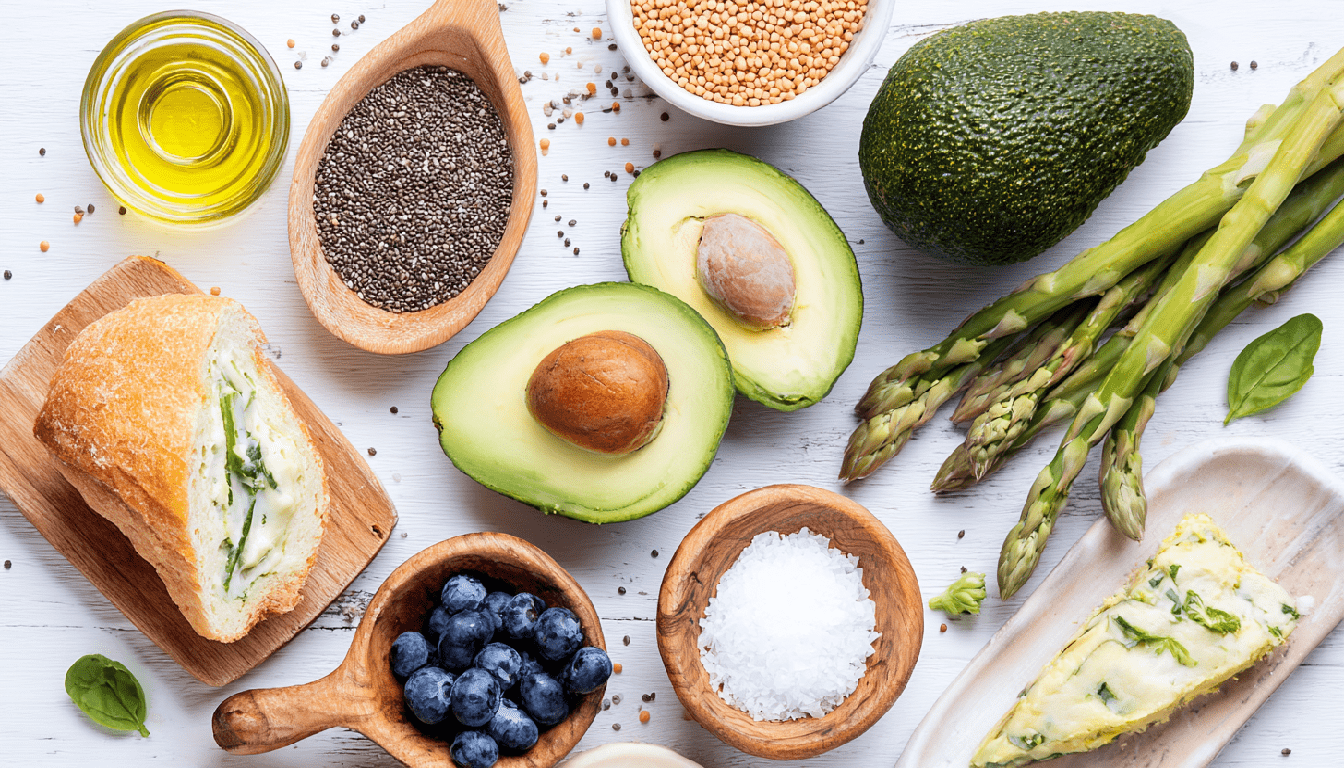

- Нутрициологическая поддержка и диетотерапия:

Питание должно быть частью лечебного плана. Рекомендуется противовоспалительный рацион:

- увеличение потребления омега-3 ПНЖК (жирная рыба, льняное масло, грецкие орехи) для подавления воспаления;

- достаточное количество белка и специфических аминокислот (глицин, пролин) — строительного материала для хряща;

- исключение/сокращение продуктов, провоцирующих системное воспаление: простые сахара, ультраобработанные продукты, избыток омега-6 жирных кислот (подсолнечное, кукурузное масло), глютен и молочные продукты при их индивидуальной непереносимости;

- коррекция выявленных дефицитов витаминов и минералов на основе данных чек-апа.

Питание также играет роль. Рацион с противовоспалительным акцентом и достаточное потребление воды поддерживают нормальную среду внутри сустава.